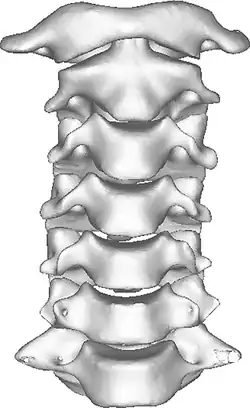

Once there is an onset of the symptoms in the patient, the patients are screened through cervical-spinal imaging techniques: X-ray, CT, MRI. The scanning technique points out any cervical vertebrae defects and misalignments. (Image 1. and 2.) When cervicocranial syndrome is caused as a result of a genetic disease, then family history and genetic testing aid in making an accurate diagnosis of cervicocranial syndrome.